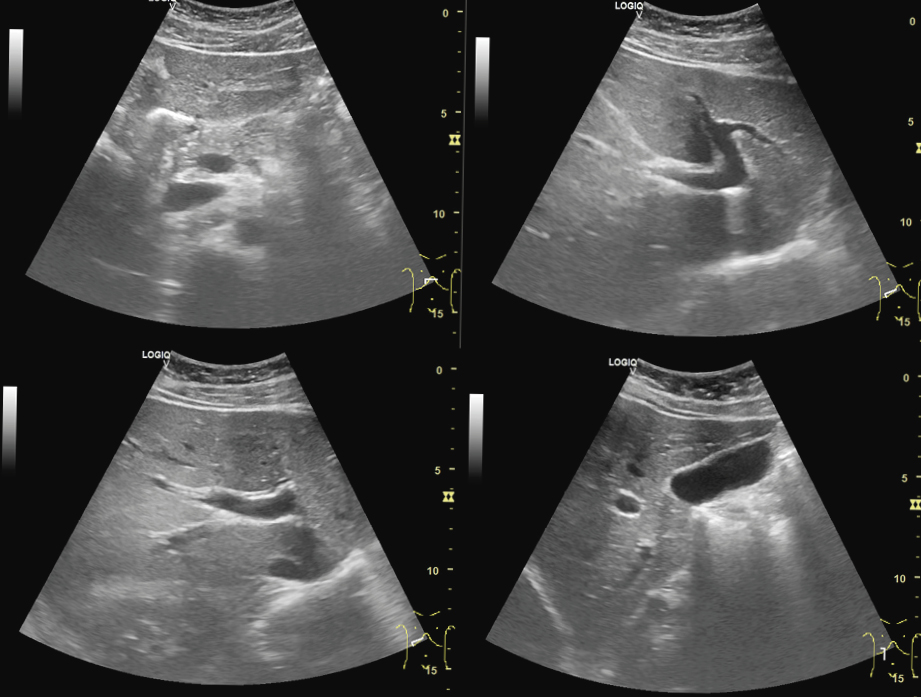

하지만 치료 71일째 되는 날, 유도 대련을 하던 중 다쳐 MRI 검사상 우측 전방십자인대가 파열(grade 3, complete)됐다고 연락이 왔다(그림2).

2.jpg

그림2. 우측 전방십자인대 파열로 진단된 환자의 (A) Sagittal Proton Density-weighted Fat-Suppressed and (B) Sagittal T1 MRI 영상; 전방십자인대 재건술 후 (C) Antero-Posterior 및 (D) Lateral X-ray 영상

“I think there is no holistic way to rejuvenate a big ligament that is completely torn. Do you agree?” (완전히 파열된 큰 인대를 회복시킬 수 있는 전체론적 방법이 없다고 생각되는데요. 원장님도 그렇게 보시나요?)

나는 전방십자인대의 완전 파열은 일반적으로 수술 치료가 권장되며, 수술 후 회복 및 재활 과정에서 한의학적 치료가 효과적이라 안내했다. 수술 후 환자는 다시 본원에 내원했고, 수술 후 회복과 재활을 위해 침구 치료 및 한약을 적극 활용했다. 이 과정에서 트라마돌과 같이 마약성 진통제로 분류될 수 있는 화학 약물 사용도 최소로 줄일 것을 권고했다.

결과적으로 환자의 우측 무릎 상태는 잘 회복돼 수술 4개월 만에 자전거를 탈 수 있게 됐다.